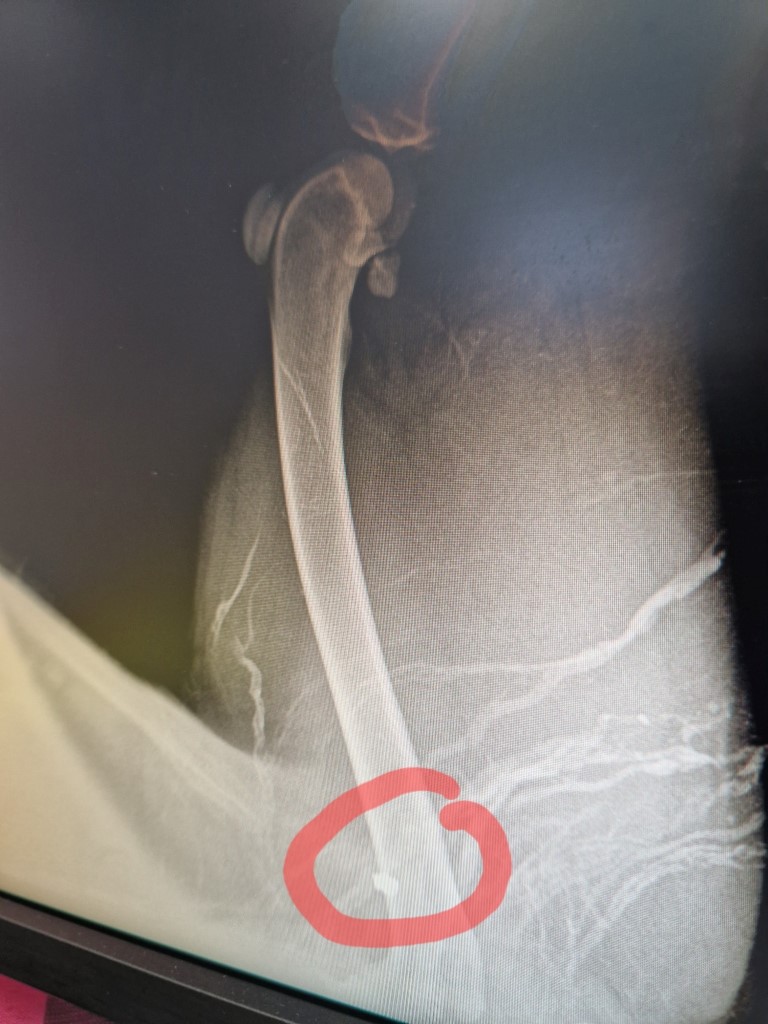

„Поредната жертва на човека. Отново Павел баня и отново насилие. Кучето е стреляно. С множество рани и една съчма в крака. С последни сили влачейки се, се е добрало до входа на един от големите хотели в града. Сигнализираха ни загрижени жени. Зарязахме всичко и тръгнахме. Закарахме го по спешност в клиника ,защото имаше голяма кръвозагуба. От там сигнал на 112, разпит и писмени показания. До кога ще продължава това?“, съобщават от Animal Hope – Кazanlak.

Снимки: Animal Hope – Кazanlak